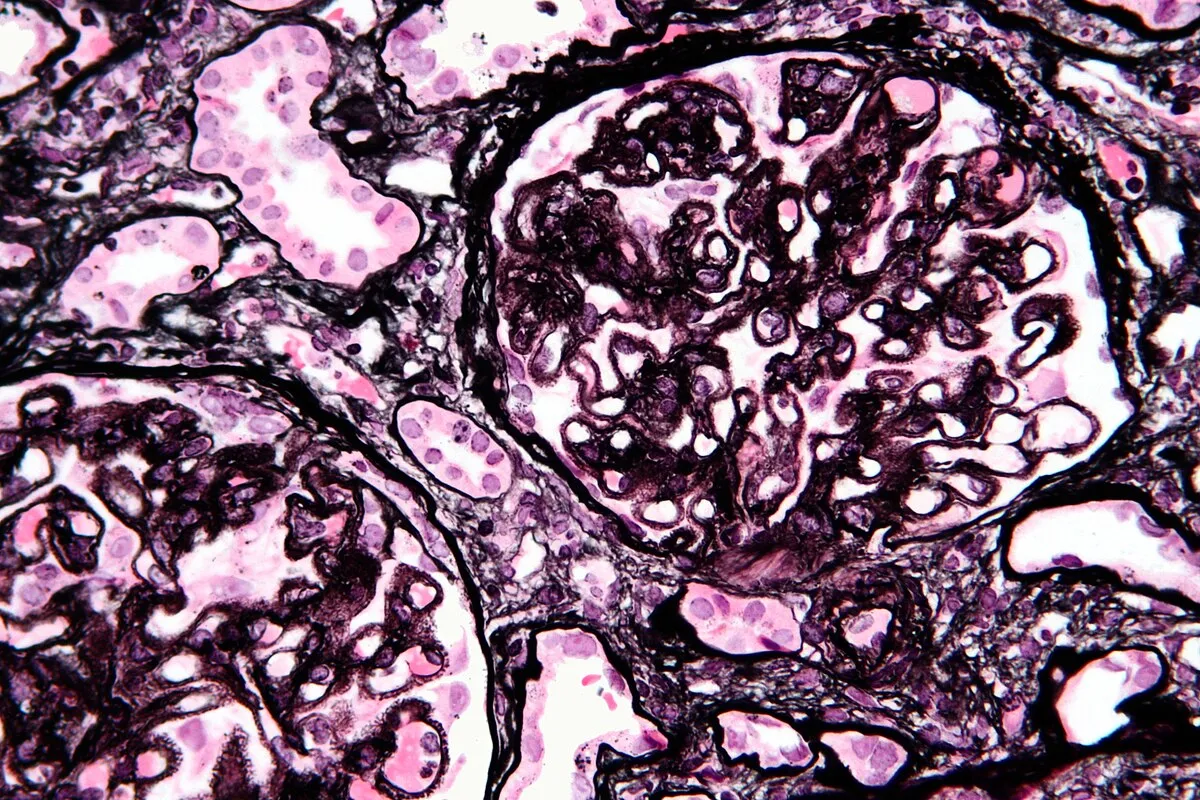

Amiloidose renal: aspectos sobre patogenia, diagnóstico e proteomica

Amiloidose renal: aspectos sobre patogenia, diagnóstico e proteomica

Este vídeo apresenta, de forma didática e baseada em evidências, os principais achados da tese de doutorado sobre amiloidose renal, com foco em proteômica glomerular e ativação do complemento. São discutidos aspectos diagnósticos, implicações fisiopatológicas e correlações clínico-patológicas relevantes para a prática do nefrologista. O conteúdo sintetiza dados inéditos de matriz extracelular glomerular e diferencia perfis entre subtipos de amiloidose. Trata-se de um material aprofundado e acessível, ideal para atualização de especialistas na área.